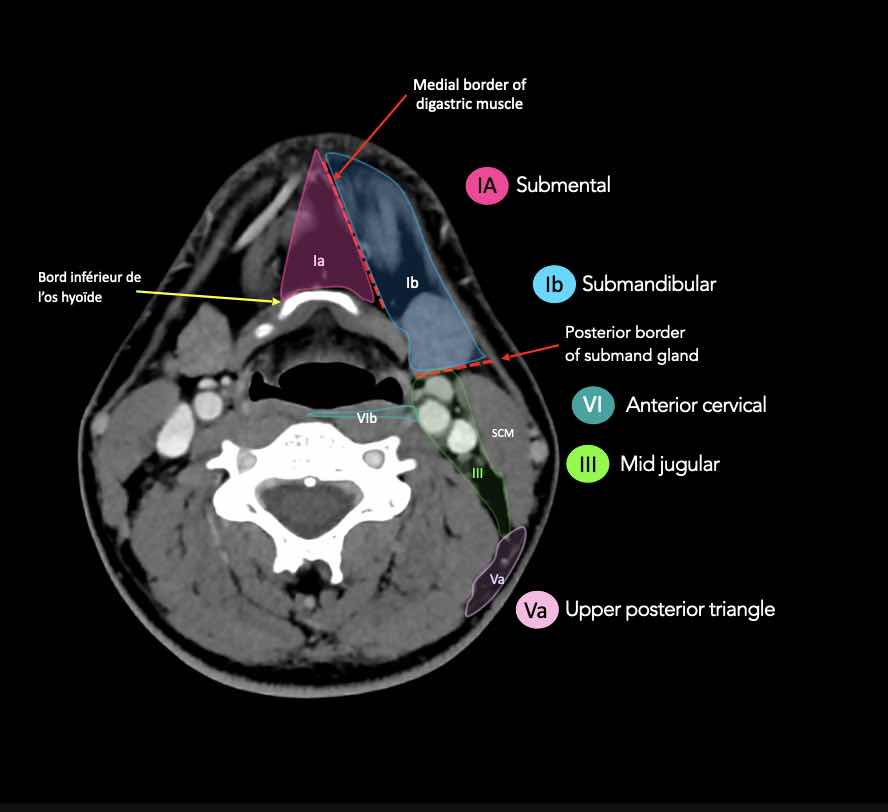

CT Scan Mặt Cắt Ngang (Axial CT)

Các lát cắt CT mặt phẳng ngang tương ứng với hình minh họa tổng quan.

Các lát cắt CT mặt phẳng ngang với hình ảnh chi tiết hơn.

Nhấp vào hình ảnh để phóng to.

I – Dưới cằm và dưới hàm

Các hạch bạch huyết ở tầng I có nguy cơ phát triển di căn từ các ung thư khoang miệng, hốc mũi trước, mô mềm vùng mặt giữa và tuyến dưới hàm.

Tầng Ia

là vùng giữa nằm giữa bụng trước của các cơ nhị thân, chứa các hạch dưới cằm.

Tầng Ib

chứa các hạch dưới hàm nằm trong khoang giữa mặt trong của xương hàm dưới ở phía ngoài và cơ nhị thân ở phía trong, từ khớp mu cằm ở phía trước đến tuyến dưới hàm ở phía sau.

III – Tĩnh mạch cảnh giữa

Tầng III nhận các bạch mạch hướng tâm từ tầng II và V, và một số bạch mạch hướng tâm từ các hạch sau hầu, trước khí quản và thần kinh thanh quản quặt ngược.

Tầng này thu nhận bạch huyết từ đáy lưỡi, amidan, thanh quản, hạ hầu và tuyến giáp.

Bờ dưới của sụn nhẫn là ranh giới giữa tầng III và tầng IVA.

Các hạch bạch huyết ở tầng III có nguy cơ chứa di căn từ các ung thư khoang miệng, vòm hầu, hầu miệng, hạ hầu và thanh quản.

VI – Cổ trước

Tầng này chứa các hạch tĩnh mạch cảnh trước nông (tầng VIa) và các hạch sâu hơn bao gồm hạch trước thanh quản, trước khí quản, cạnh khí quản và hạch thần kinh thanh quản quặt ngược (tầng VIb).